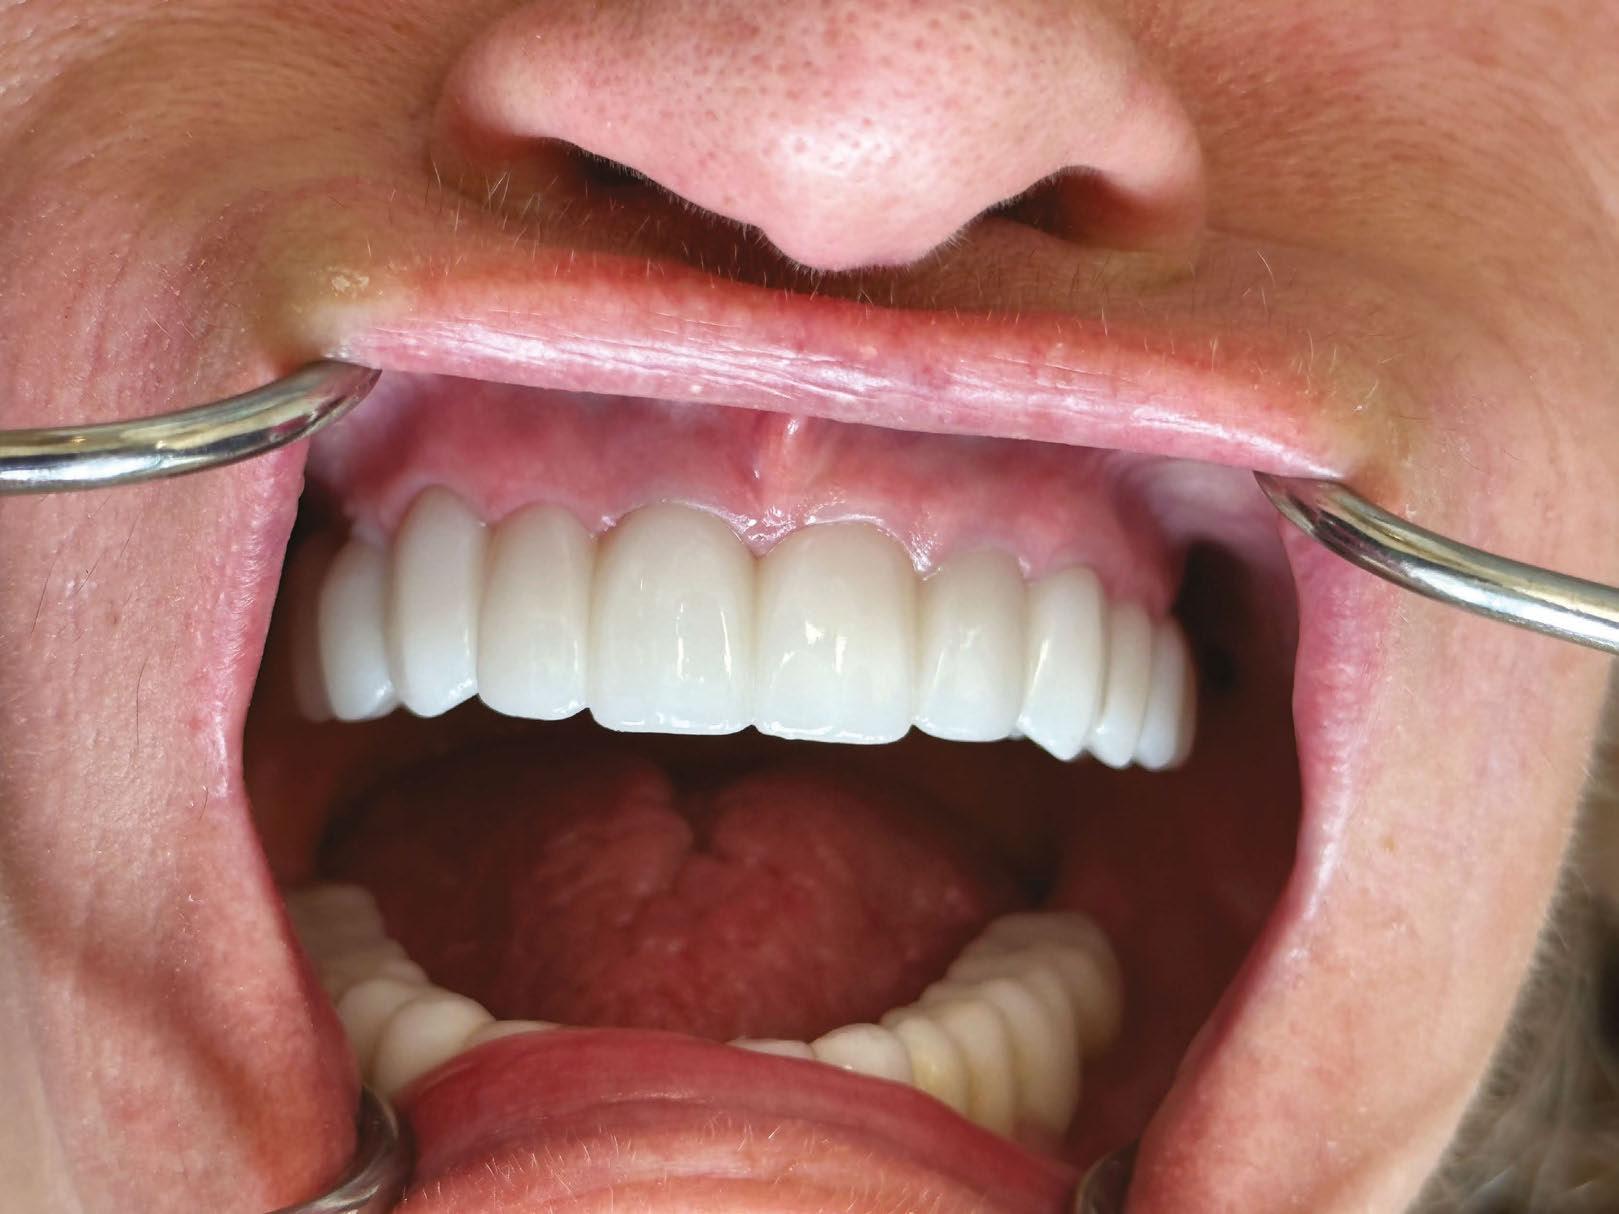

Probing tissue 3-months after 3 on 6 surgery with about 5 mm of tissue above the TRI implants

3 on 6 final result with three zirconia bridges seated. Thinner teeth and no artificial gums make it look and feel more natural

The concept behind the 3 on 6™ is elegantly simple and biomechanically sound: six dental implants are placed to support one solid arch of teeth, providing cross-arch stabilization. After allowing time for osseointegration, the single arch is replaced with three segmented zirconia bridges — one on the anterior and one on each posterior quadrant. No bone removal necessary. No artificial gum material. No bulky prosthetics. Just permanent, implant-supported teeth that feel and function more like the real thing.

This segmentation turned out to be a game-changer. Unlike a monolithic denture-like restoration, segmented bridges allowed for healthier force distribution, improved hygiene, and superior phonetics. Patients retained their natural bone architecture, which allowed for better esthetics and long-term oral health. Because the bridges sat directly over the ridge rather than floating over pink acrylic, food impaction was minimized — and when it did occur, cleaning was far more manageable. There were also nearly no cases of prosthetic fractures with the final segmented zirconia bridges, and in cases where there were needs for replacement, it was much cheaper and easier to replace a 4-unit bridge than an entire full-arch fixed prosthetic.

Most importantly, patients loved the feel. The 3 on 6™ doesn’t rely on the palate for stability, doesn’t need to be removed for cleaning, and doesn’t simulate tissue — it replaces only the teeth. For patients who had struggled with dentures or the “false” feeling of All-on-4, this was a restoration that felt like they had their real teeth back.